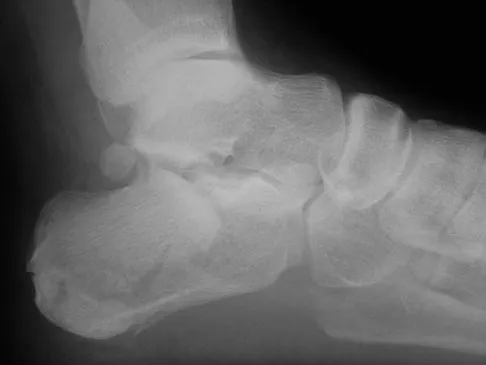

Figures 33a and 33b show the radiographs of a 10-year-old girl who reports a 4-month history of medial foot pain after she was kicked while playing soccer. The pain is worse with activity and partially relieved by rest. Examination reveals tenderness directly over a prominent navicular tuberosity. Management should consist of

An accessory tarsal navicular is located at the medial tuberosity of the navicular bone. Nearly all children and adolescents who have a symptomatic accessory tarsal navicular bone become asymptomatic when they reach skeletal maturity. Initial management should include activity restrictions, shoe modification to avoid pressure over the prominent navicular, and non-narcotic analgesics. Although anecdotal, the use of arch supports may be helpful. When pain is refractory to these methods, a short period of cast immobilization may be useful. Surgery should be reserved for patients who have disabling symptoms despite a prolonged period of nonsurgical management. When surgery is indicated, simple excision of the accessory navicular is recommended. Sella EJ, Lawson JP, Ogden JA: The accessory navicular synchondrosis. Clin Orthop 1986;209:280-285.